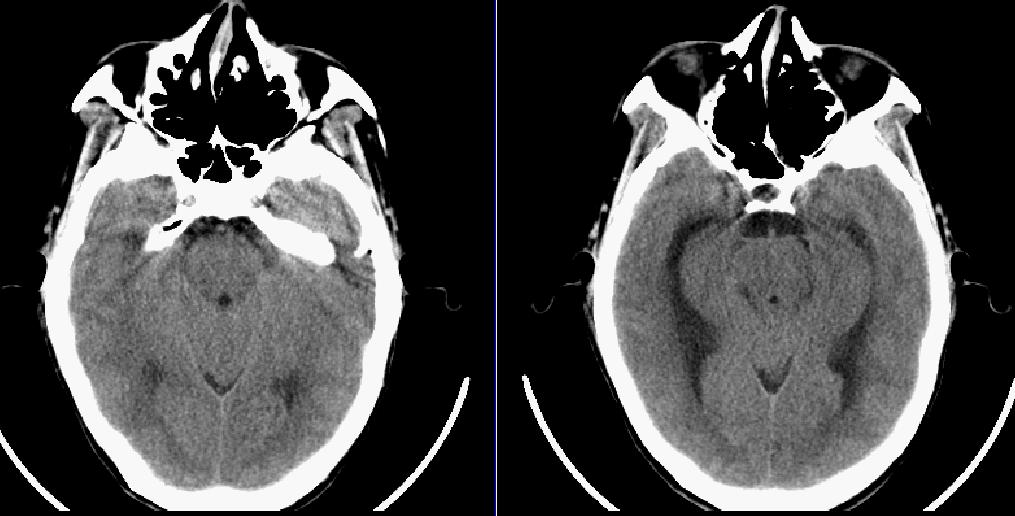

患者,女,32岁,因胆囊结石入院,手术非常成功,准备出院,突然却昏迷不醒,ct检查发现。。。。。

弥漫性脑梗塞致脑水肿、脑积水。(桥中脑多发低密度区)

临床上考虑的结核性脑膜炎,现在正在查脑脊液。